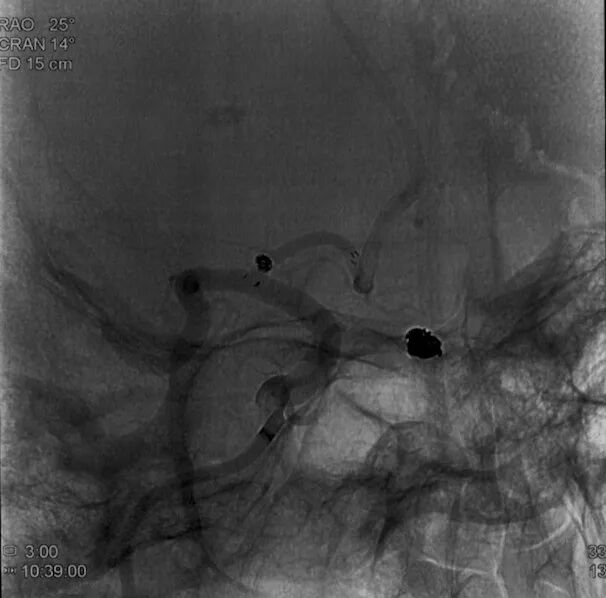

工作位正位造影(图片)

工作位正位造影(视频)

术前外院 DSA 2025-02

箭头所指右侧A1微小动脉瘤

6F Envoy DA在泥鳅导丝辅助下超选至右侧颈内动脉海绵窦段后膝。